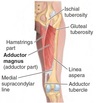

Name muscle A

A - Adductor magnus

What are the origin and insertion sites for muscle A?

Origin - Intertrochanteric line, medial lip of linea aspera of femur

Insertion - Quadriceps femoris tendon and medial border of patella

A - Vastus medialis